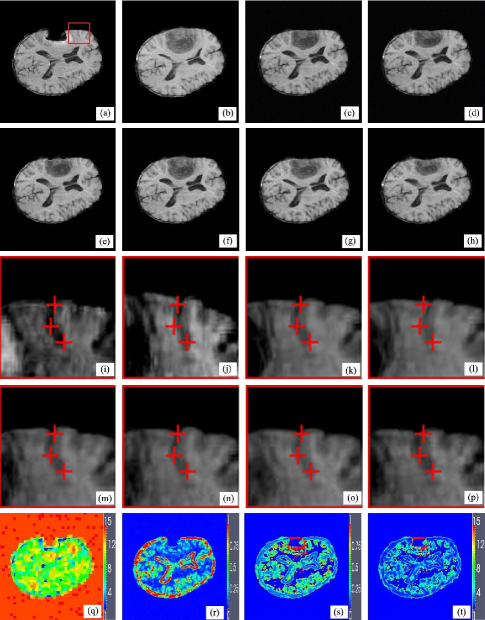

The first experiment involves matching pre- and post-operative brain tumor resection images. Brain tissue severely suppressed by tumor in the preoperative image (Fig. 3(a)(b)) expands after tumor resection, which introduces not only the missing correspondence of tumor in the post-operative images but also the local large deformations caused by the brain shift. Fig. 3(c)-(h) are the registered results of the proposed method, the previous method, AMI, AMM, DDD and BMI. Visual inspection has revealed that the proposed method, the previous method, AMI and AMM methods apparently perform better than the DDD and BMI methods because the local brain deformation resulted from the latter two methods is either insufficient or somewhat excessive. The deformations of the sulcus near the missing corresponding tumor region in Fig. 3(a)-(h) are emphatically illustrated in Fig. 3(i)-(p). Comparing Fig. 3(k) with Fig.3(l) shows the improvement of the proposed method to the previous method in registration accuracy. The structure scale map, JSM, mismatch scale map and kernel scale maps at the finest resolution of the images for the proposed method are shown in Fig. 3(q)-(t).